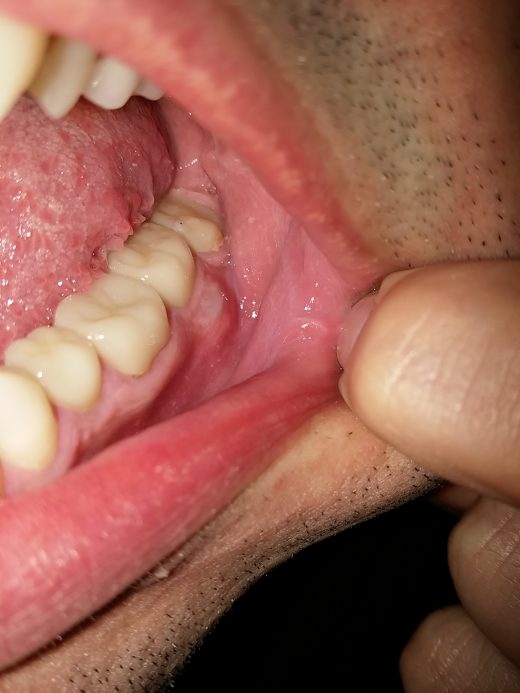

La Parodontologia è un ramo dell’Odontoiatria, che si occupa dello studio delle malattie che riguardano la bocca ed in modo particolare dei denti. Il parodonto è costituito da : gengiva; osso alveolare; cemento radicolare...